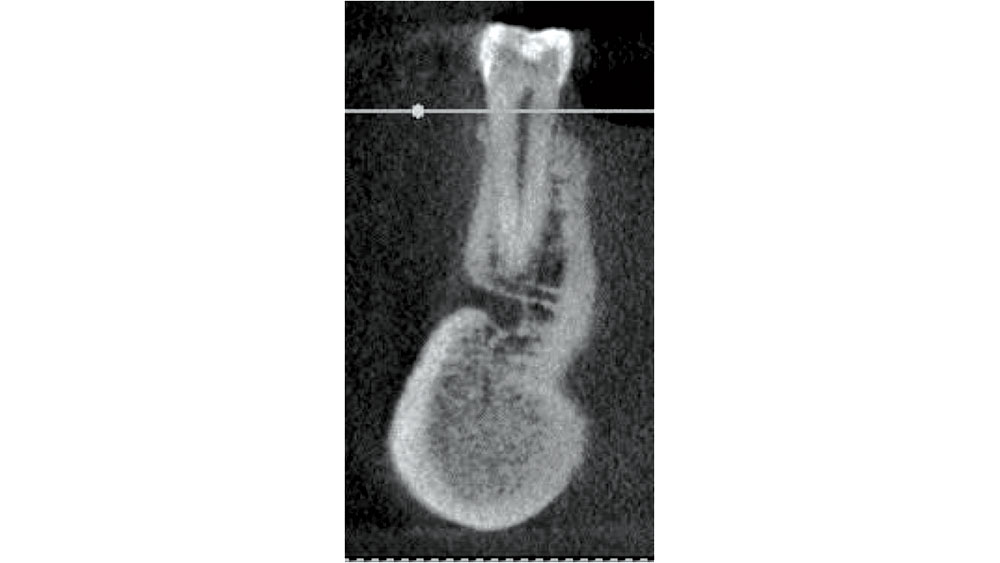

In the mandibular premolar area, 25–38 percent of the time, the mental foramen is superior to the apex of either of these teeth.6 The location of the mental foramen is highly variable, but most commonly located in the 1st or 2nd premolar area. If a premolar is indicated for extraction, CBCT measurements should be completed to confirm adequate bone below the apex. The clinician must be careful in debriding this area as nerve impairment may occur (Fig. 8).

Figure 8

Figure 8: Mandibular premolar proximity to mental foramen.